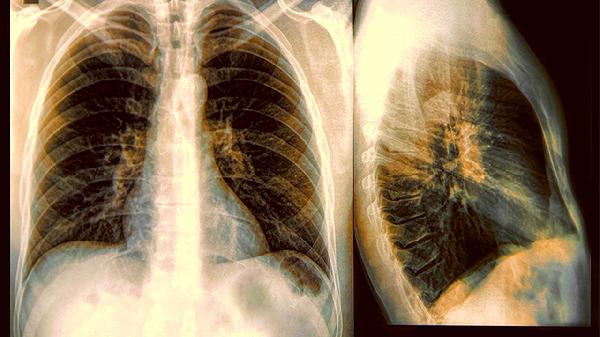

胸部CT报告上"磨玻璃影"三个字,比"结节"更值得警惕。定期体检的人群要建立自己的影像资料库,方便医生对比观察变化。